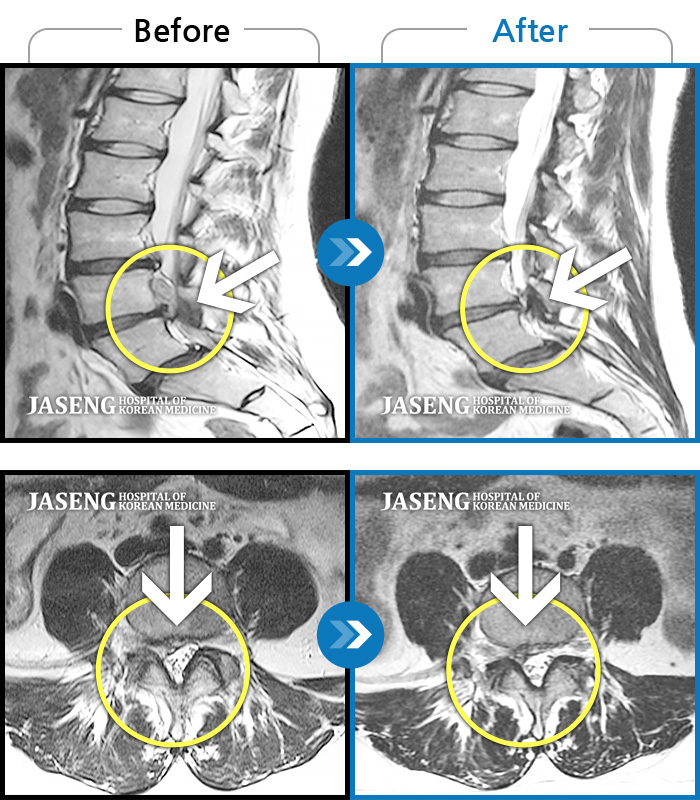

허리디스크

보라매 · 왕오호 원장

좌측 허리 통증 및 좌측 다리 저림

촬영시기

2016.05.21 ~ 2018.04.13

2018.12.28